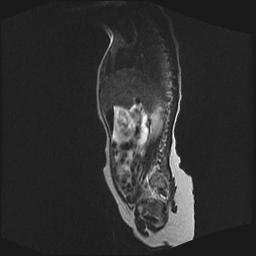

四个月的女婴,ct示脊膜膨出.

脊柱裂、脊膜膨出,请结合临床除外皮毛窦。

脂肪脊髓脊膜膨出

脊柱裂、脊膜膨出